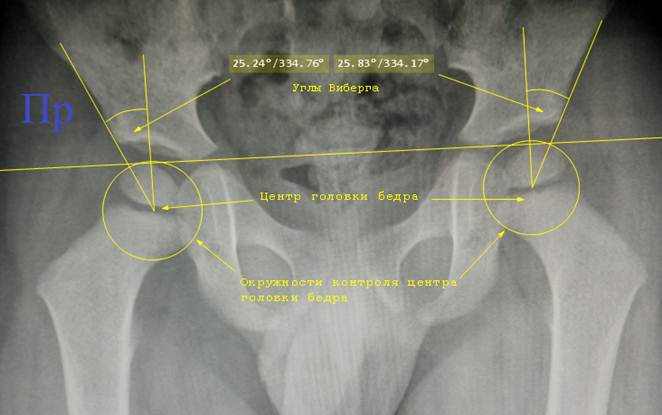

Угол

Виберга. Для его определения нужно

отметить центр головки бедра. Как правило, он находится в середине экватора

головки. Для того, чтобы проверить правильность отметки, берут циркуль, его

ножку ставят в отмеченный центр, а грифель на наружный край экватора головки.

Очерчивают окружность, она должна близко совпадать с краем тени головки и не

пересекать крышу вертлужной впадины. Мы при выполнении проверки окружностью не

прижимаем грифель циркуля к пленке, а просто ведем его кончик у изображения и

следим за положением. Это позволяет проверить центр и избежать лишних линий на

снимке. Затем из отмеченного центра проводят две линии: перпендикуляр к линии

Хильгенрейнера и касательную к краю вертлужной впадины. Здесь тоже нельзя

забывать про лимбус – если он виден, то линию надо вести к краю лимбуса. Угол

между линиями и будет углом Виберга, или center edge angle, CEA.

Снимок

таза ребенка 4 лет. Отмечены центры

головок бёдер, что непросто из – за их

пока ещё слабой оссификации. Они обычно находятся посередине полоски зоны роста. Центры головок

бёдер проверены окружностями.

Относительно линии Хильгенрейнера и наружного края контура вертлужной

впадины начерчены углы Виберга.

таза ребенка 14 лет. Расчерчивание для определения угла Виберга на снимках

старших детей выполнять проще.